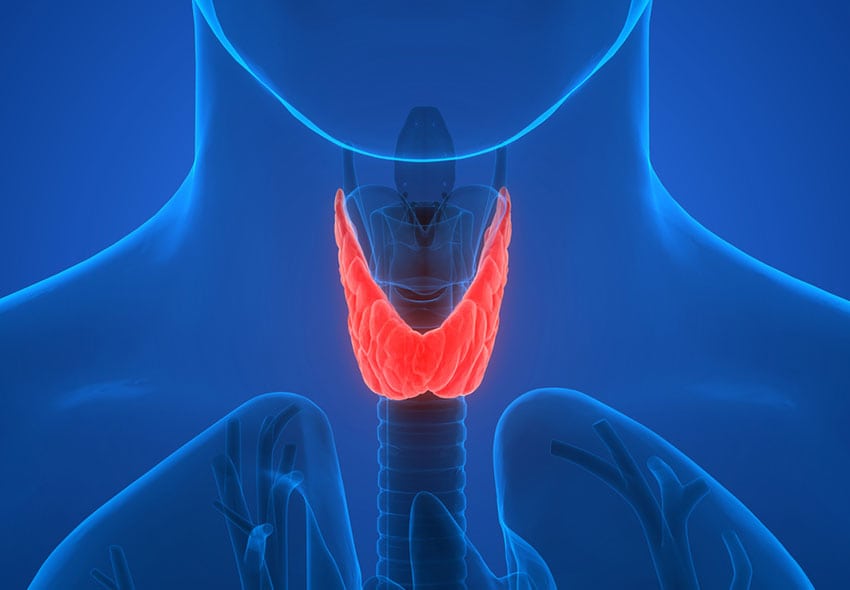

Impacto del COVID sobre la tiroides

¿Cuál es el impacto del COVID sobre la tiroides? Oded Stempa responde las dudas que tienen cuentahabientes. Después de la gripe española, el Covid 19, es la pandemia más letal y de más rápida propagación de la que se tenga registro. Alrededor de 6,3 millones de personas han muerto a nivel mundial a consecuencia de la […]

Oda a la tiroides

Les vamos a dar unas clases infernales sobre la tiroides, qué es, cuál es su función y tooodos los tipos de enfermedades que vienen de ella.

¿Qué onda con los nódulos tiroideos?

Les vamos a dar clases de tiroides, para qué sirven, qué hacen en nuestro cuerpo, y qué onda con los nódulos, qué son y cuándo debemos preocuparnos.

Tiroides: hipotiroidismo e hipertiroidismo

Les vamos a dar una clase INFERNAL sobre tiroides: Cuál es su función, cómo lo hace y qué regula en el cuerpo.